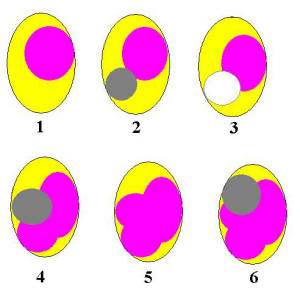

Gráfico del corte

transversal de una pieza dental y su conducto, mostrando la

secuencia de condensación lateral:

|

- Cono maestro insertado

Ver

conometria.

- Cemento y cono maestro insertado, en gris oscuro

condensador digital presionando lateralmente al cono maestro

para hacer espacio para un cono accesorio

- Espacio dejado por el espaciador digital para el cono

accesorio

- Colocación de un nuevo cono accesorio y colocación del

condensador digital, para generar un nuevo espacio.

- Colocación de otro cono accesorio.

- Y se realiza un nuevo espacio con el condensador

digital. Así sucesivamente hasta el relleno tridimensional

de conos y cemento sellador.